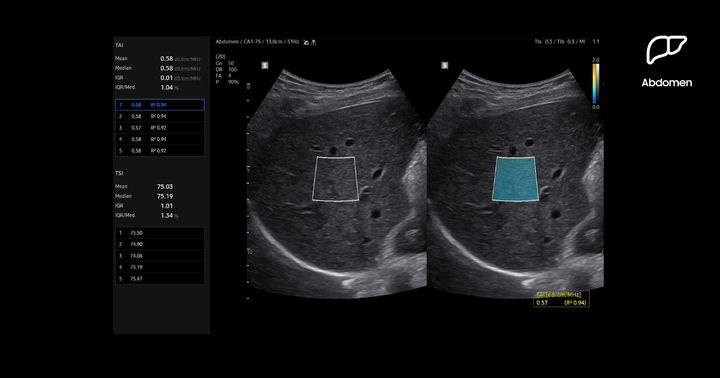

[서울=뉴시스] 삼성메디슨은 지난 9월 대한영상의학회 (KCR 2025)를 통해 영상의학과 프리미엄 초음파 진단기기 R20을 국내에 공개했다. R20은 간 지방 정량 측정 AI 기반 기능을 통해 정밀한 진단을 가능하게 한다. 티에이아이 (TAI·Tissue Attenuation Imaging)는 초음파 신호를 간세포 내 지방에 의해 약해지는 정도를 측정해 실시간으로 지방간 변화를 평가한다. (사진=삼성메디슨 제공) 2025.11.24. [email protected] *재판매 및 DB 금지

특히, R20은 간 지방 정량 측정 AI 기반 기능을 통해 정밀한 진단을 가능하게 한다. 티에이아이 (TAI·Tissue Attenuation Imaging)는 초음파 신호를 간세포 내 지방에 의해 약해지는 정도를 측정해 실시간으로 지방간 변화를 평가한다. 티에스아이 (TSI·Tissue Scatter distribution Imaging)는 조직 산란 분포를 정량적으로 측정해 지방간 진행 상황을 모니터링한다.